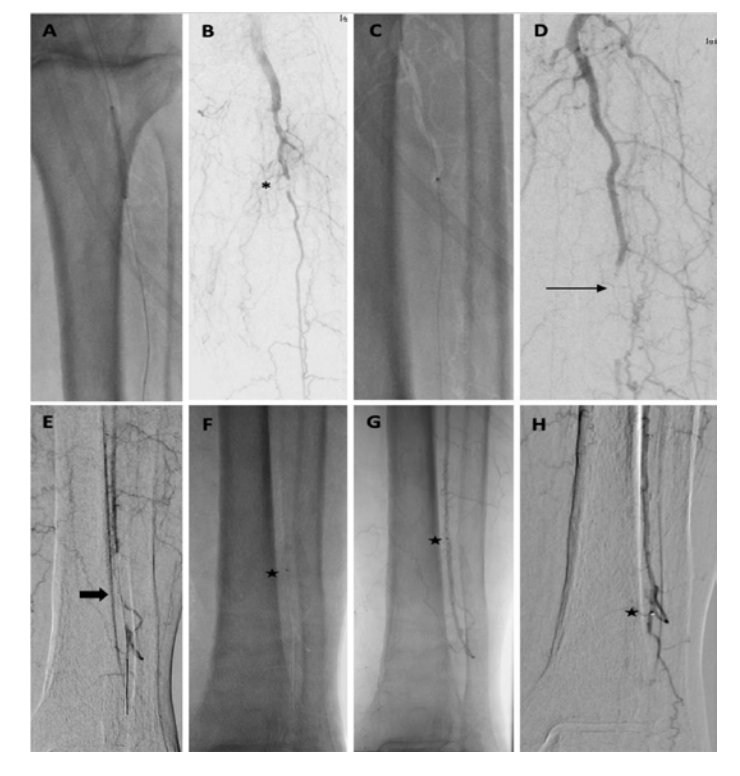

Diagnostic angiography (Figure 3) revealed a long-segment occlusion of the femoropoliteal artery beginning approximately 10 cm from the origin of the superficial femoral artery, at the level of the arteriovenous fistula. Numerous collaterals from the profunda artery were seen through the thigh and knee. There was faint reconstitution of the proximal peroneal artery. No significant below-ankle pedal reconstitution was noted.

The repeat angiogram demonstrated restoration of flow throughout the femoropopliteal segment, with direct inline flow to the peroneal artery (Figure 4). On this study, distal peroneal artery collaterals and perforators were seen reconstituting pedal arteries, not demonstrated previously, in keeping with the patient’s markedly improved physical exam. There was near resolution of the previously identified superficial femoral arteriovenous fistula. Despite the slightly ectatic appearance of the distal popliteal artery and tibioperoneal trunk, no true aneurysmal dilation was identified on the recent CTA. An approximate 80% stenosis was present within the tibioperoneal trunk, at the same location where difficulty was encountered in advancing the wire on the previous day. Angioplasty of this segment was performed with a 3.0 x 60 mm balloon in order to improve single-vessel inline flow to the foot.

Following angioplasty, the repeat angiogram demonstrated resolution of the tibioperoneal stenosis, but with a new, nearly occlusive 5 mm filling defect in the proximal peroneal artery (Figure 5). Several therapeutic options were discussed and a decision to perform spot laser thrombolysis was made. Using a 0.9 mm Turbo-Elite laser atherectomy catheter (Philips), a total of two passes were performed across the proximal peroneal artery at low and moderate fluence and rate settings. The repeat angiogram demonstrated unsuccessful lysis, with the embolus now having migrated into the mid segment of the peroneal artery, resulting in complete occlusion. Fortunately, an .014-inch wire remained across the occlusion and a decision to perform long-segment angioplasty in order to macerate the lesion was made. The angioplasty was performed with slow and prolonged inflation of a 2.0 x 220 mm balloon, with the balloon tip in the distal peroneal artery. It also resulted in more distal migration of an occlusive filling defect, bringing complete occlusion of important, unnamed collaterals to the pedal arteries, as well as the perforating branch of the peroneal artery.

A third, final option was to perform embolectomy at this location, using an over-the-wire mechanical aspiration with a CAT3 catheter (Penumbra). After a single pass, there was flow restored to most of the distal peroneal artery, but a second pass was required in order to restore flow into the perforating branch of the peroneal artery (Figure 5). When the catheter was externalized from the groin sheath, physical exam demonstrated an unwound coil and no radiopaque marker band, consistent with shearing of the catheter tip (Figure 6). Although there was no significant resistance when removing the catheter, findings were confirmed on spot view of the ankle, which showed the radiopaque tip wedged within the perforating branch of the peroneal artery (Figure 7).